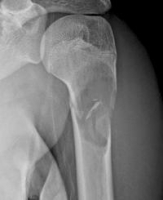

Diagnostics différentiels :

- Kyste anévrysmal

- Dysplasie fibreuse

- Fibroxanthome

- Abcés de Brodie

- Enchondrome

- Histiocytose X

- Tumeur brune d'hyper-parathyroïdie